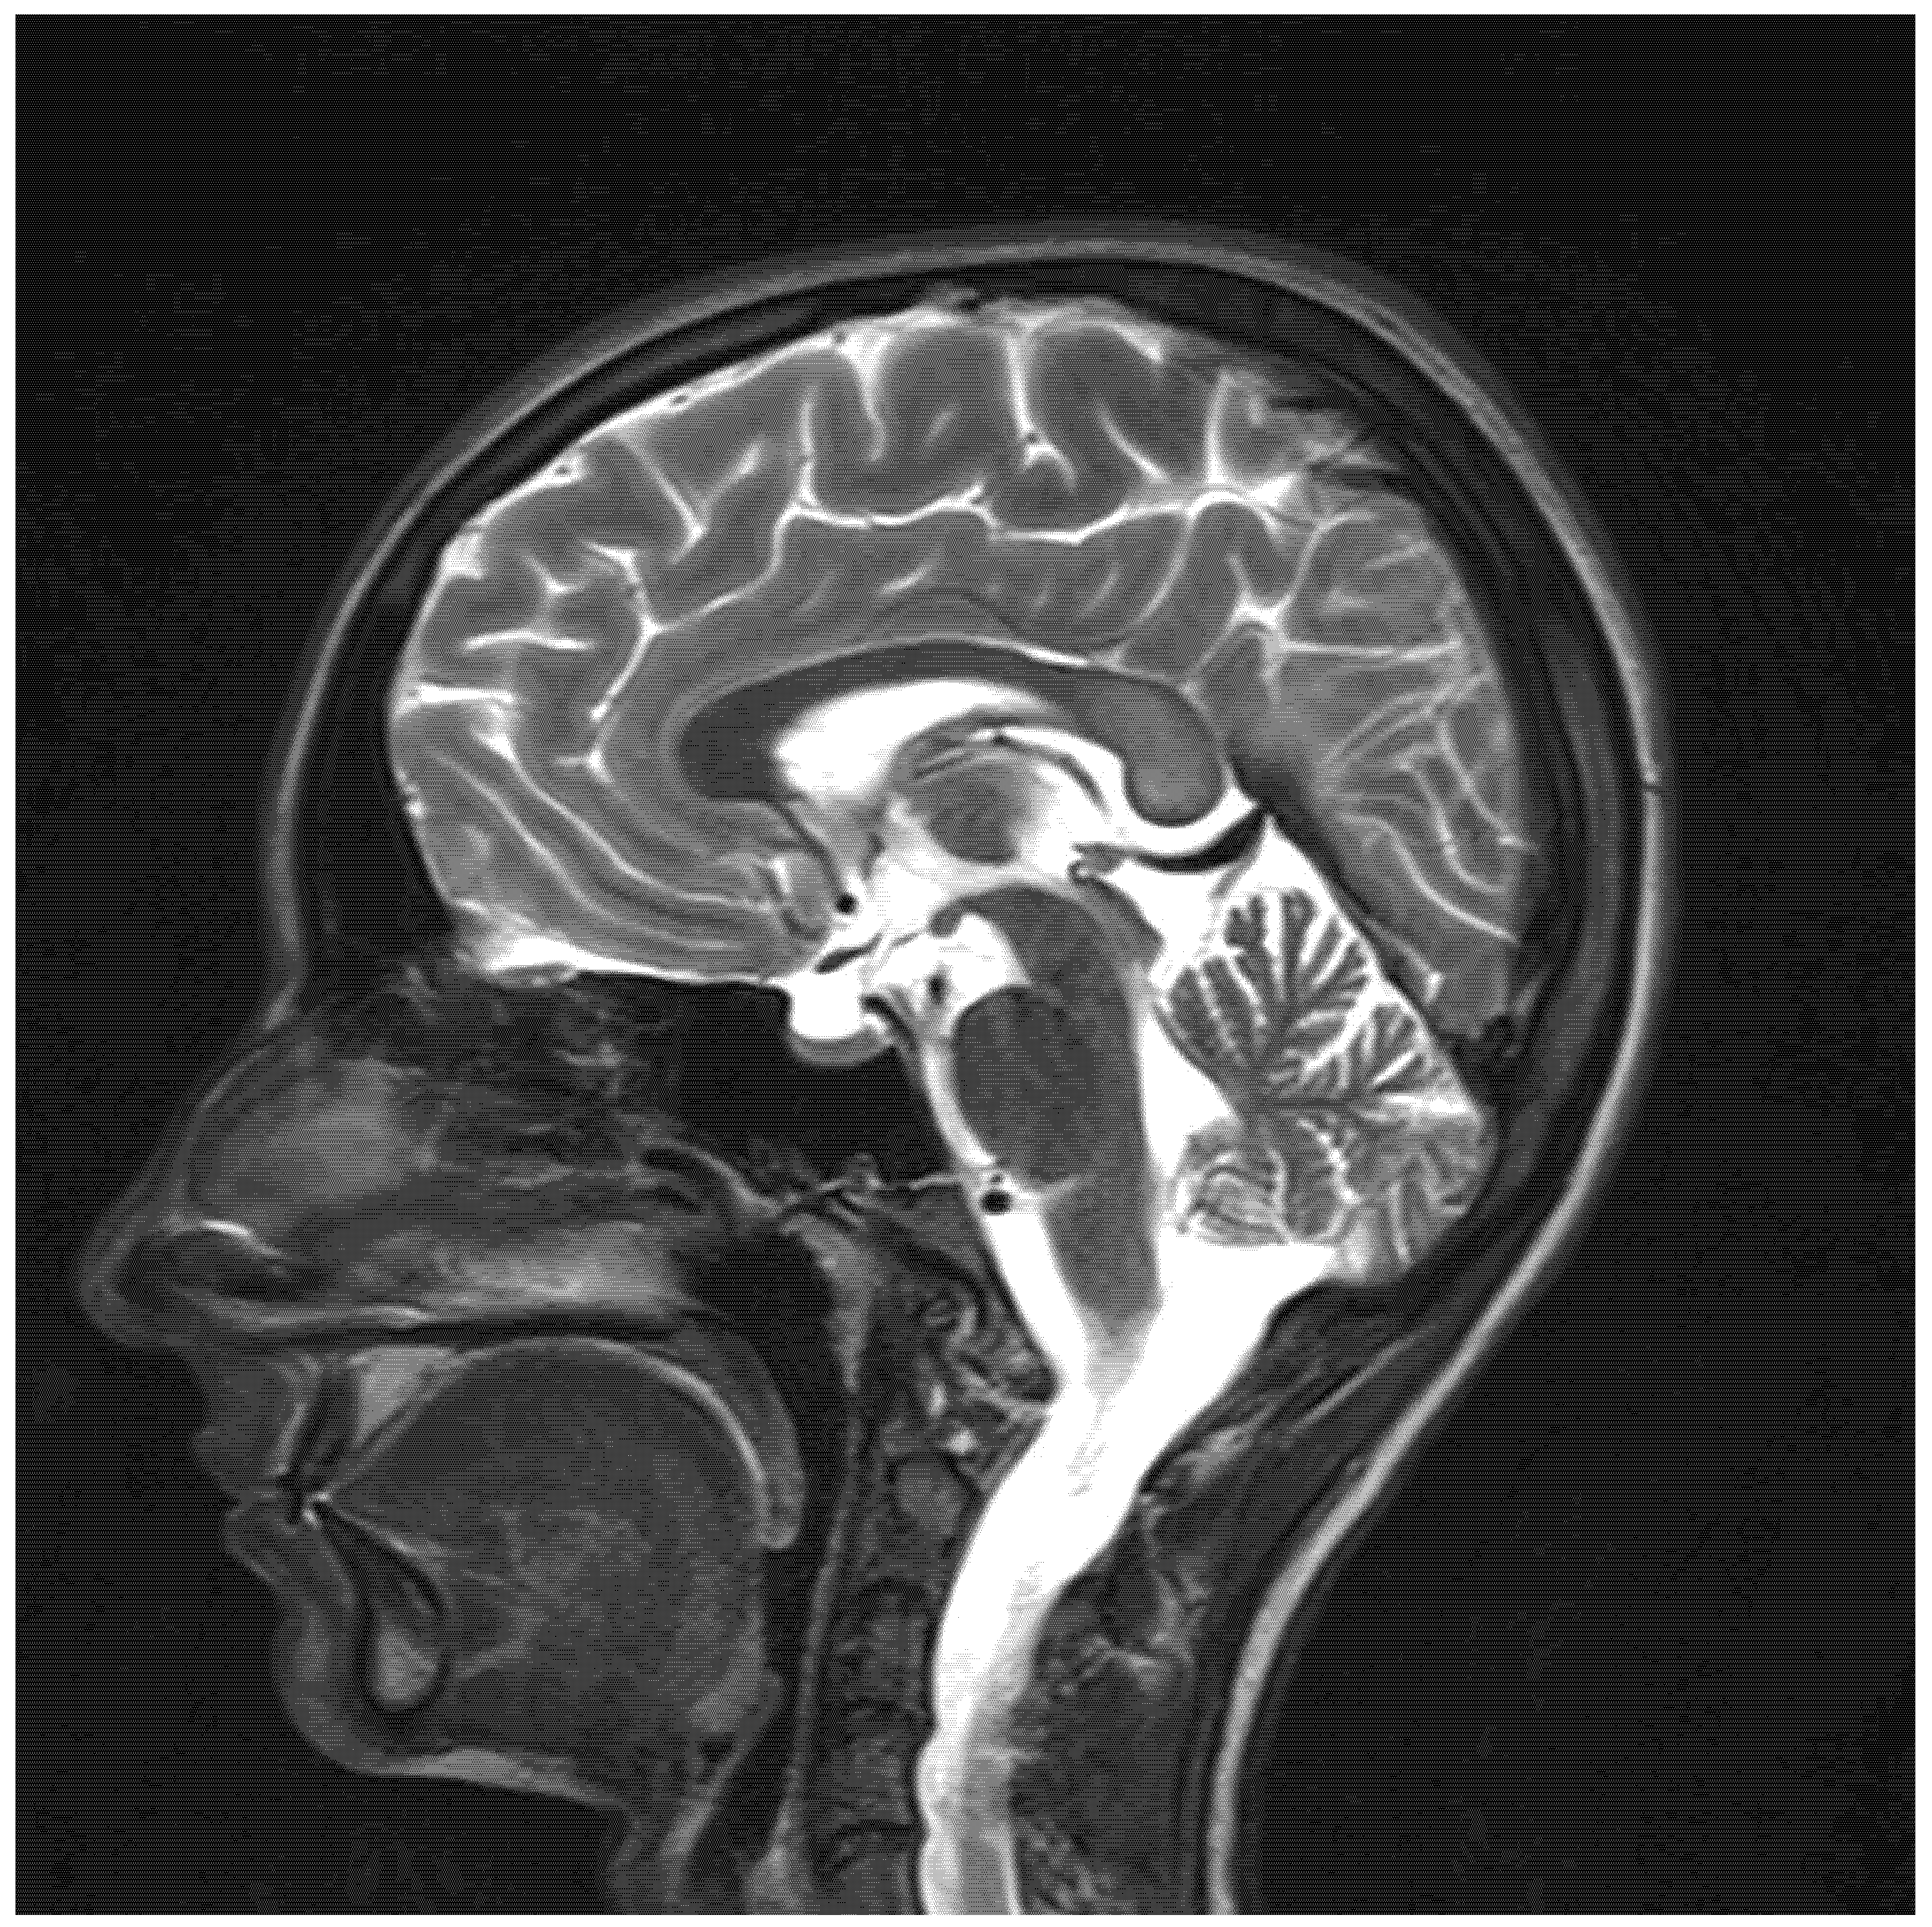

| Chang, 2021, USA [4] | 14, M | Clostridium difficile enterocolitis | N/A | N/A; N/A | Altered mental status; stiffening of 4 extremities; visual disturbance; slurred speech; gait instability | T2: symmetrical hyperintensity with corresponding diffusion restriction on DWI in posterior frontal, parietal, and occipital periventricular white matter and splenium of the corpus callosum | Near complete resolution | Near complete resolution |

| Omrani, Iran, 2020 [8] | 11, M | Febrile bloody diarrhea | 12 g | N/A; N/A | Tinnitus; hearing loss; aggressive behavior; generalized dystonia; generalized tonic-clonic seizure; decreased level of consciousness. | T2: Symmetrical hyperintensity in dentate nuclei, substantia nigra, globus pallidi, splenium of the corpus callosum, and centrum semiovale | Improvement | Partial improvement |

| Sudan, 2016, India [11] | 14, M | Acute abdominal pain | N/A | 3; 5 | Dysarthria; altered mental status; seizures. | T2: symmetrical hyperintensity in the optic tracts, dorsal midbrain, inferior olivary nuclei, peri-aqueductal white matter, superior and inferior colliculi, superior cerebellar peduncle, dentate nuclei, medulla oblongata, and cervical spinal cord segment extending from the cervicomedullary junction to C6-C7 level DWI: restricted diffusion in the splenium of the corpus callosum | N/A | Resolution |

| Sun, 2019, USA [12] | 11, M | Fusobacterium menigitis | N/A | 3 months; N/A | Vomiting; dizziness; vertigo; gait instability; bilateral lower extremity paresthesia | T2: Symmetrical hyperintensity in the dentate nuclei, dorsal pons, and medulla. DWI: no restricted diffusion | Resolution | Resolution |

| Yazdani, 2019, USA [13] | 17, M | Chronic diarrhea | N/A | N/A | Gait instability; abnormal unilateral lean | T2: Symmetrical signal hyperintensity in dorsal pons, dentate nuclei, dorsal medulla | Improvement | Resolution |